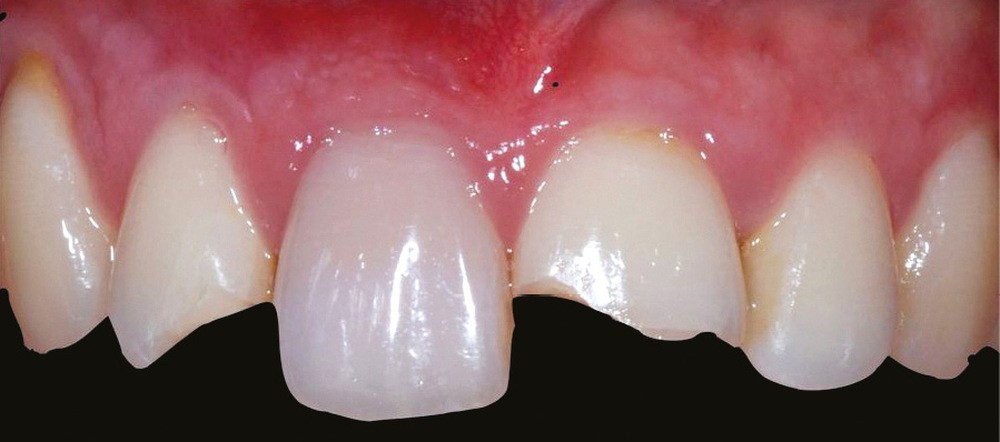

– le trauma, qui va donner une couleur plutôt rouge [4] (fig. 3) ;

– les soins conservateurs et endodontiques [5] (fig. 4 et 5).